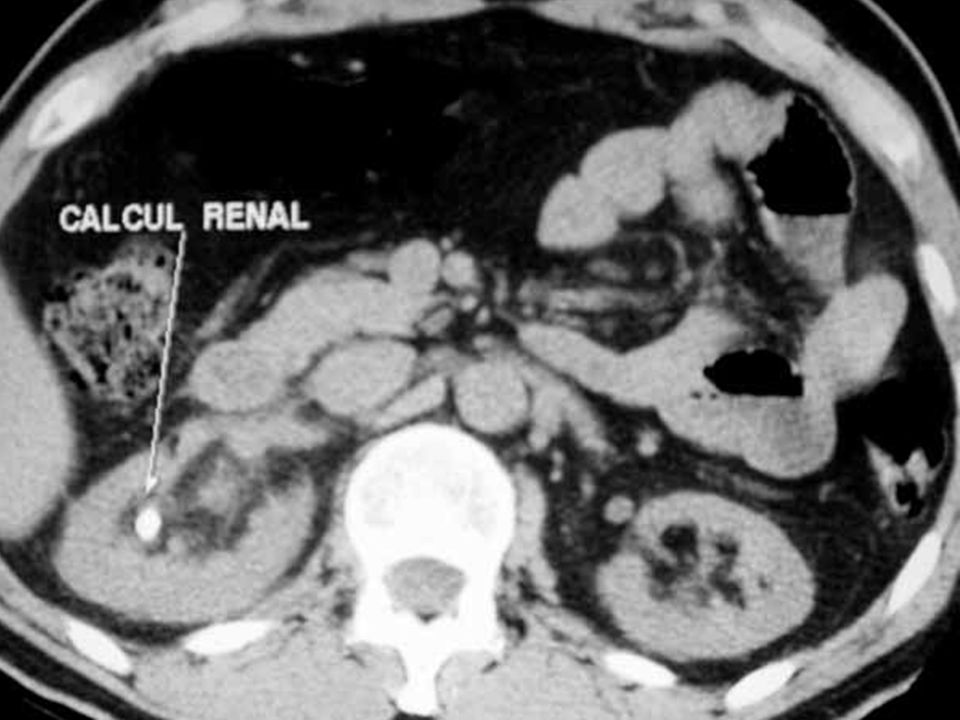

- Détecter un calcul rénal (colique néphrétique, douleurs lombaires aiguës)

Détection des calculs : fini l’incertitude

Dans mon expérience, c’est LA grande question qui tracasse : ai-je réellement un calcul ou est-ce « dans la tête » ? Grâce à l’uroscanner, même les plus petits cailloux (certains font moins de 2 mm) sont repérés comme sur une carte au trésor, évitant des semaines d’errance diagnostique. Et bonne nouvelle, l’examen aide aussi à déterminer la taille et la localisation exactes : indispensable pour prévoir un traitement adapté.